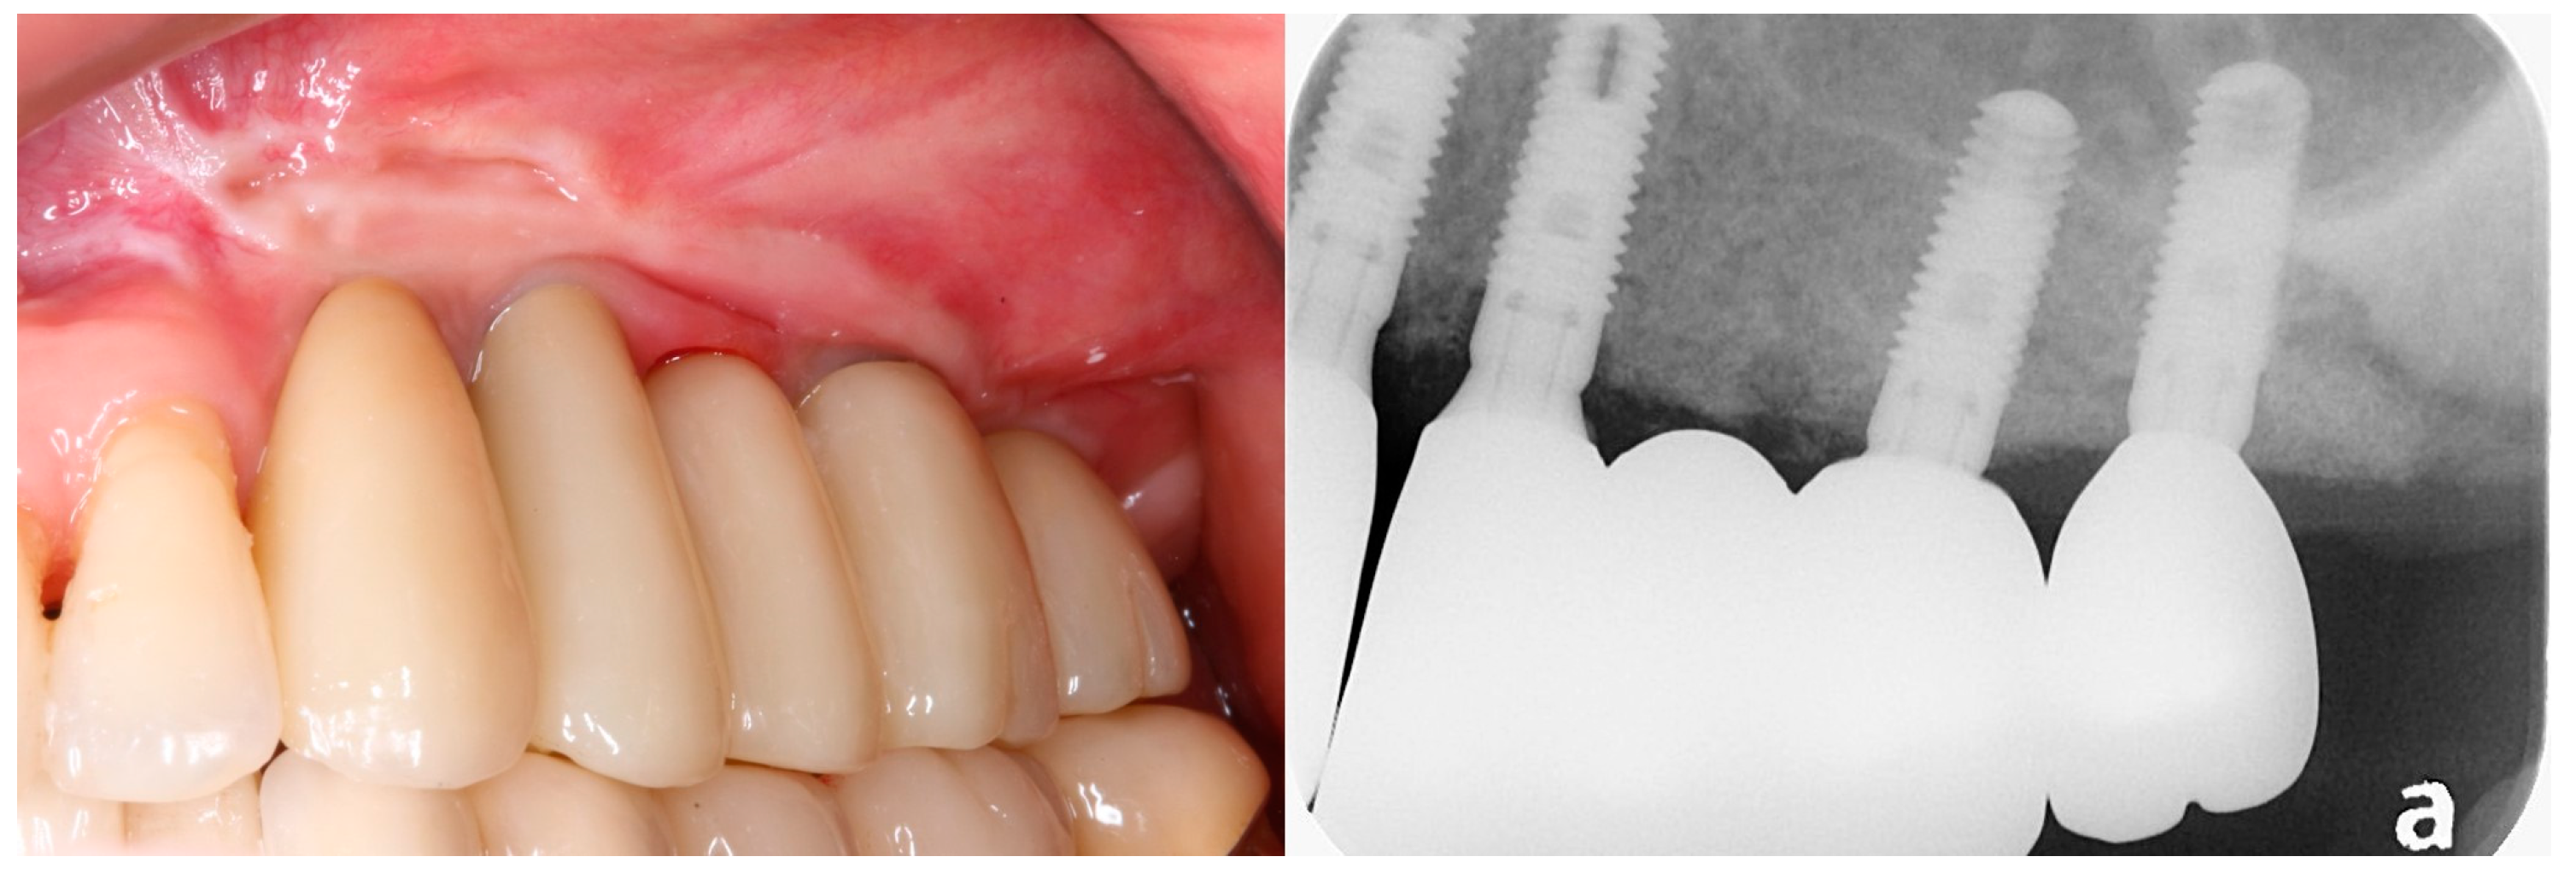

3.1. Clinical Results

3.2. Radiographic Results